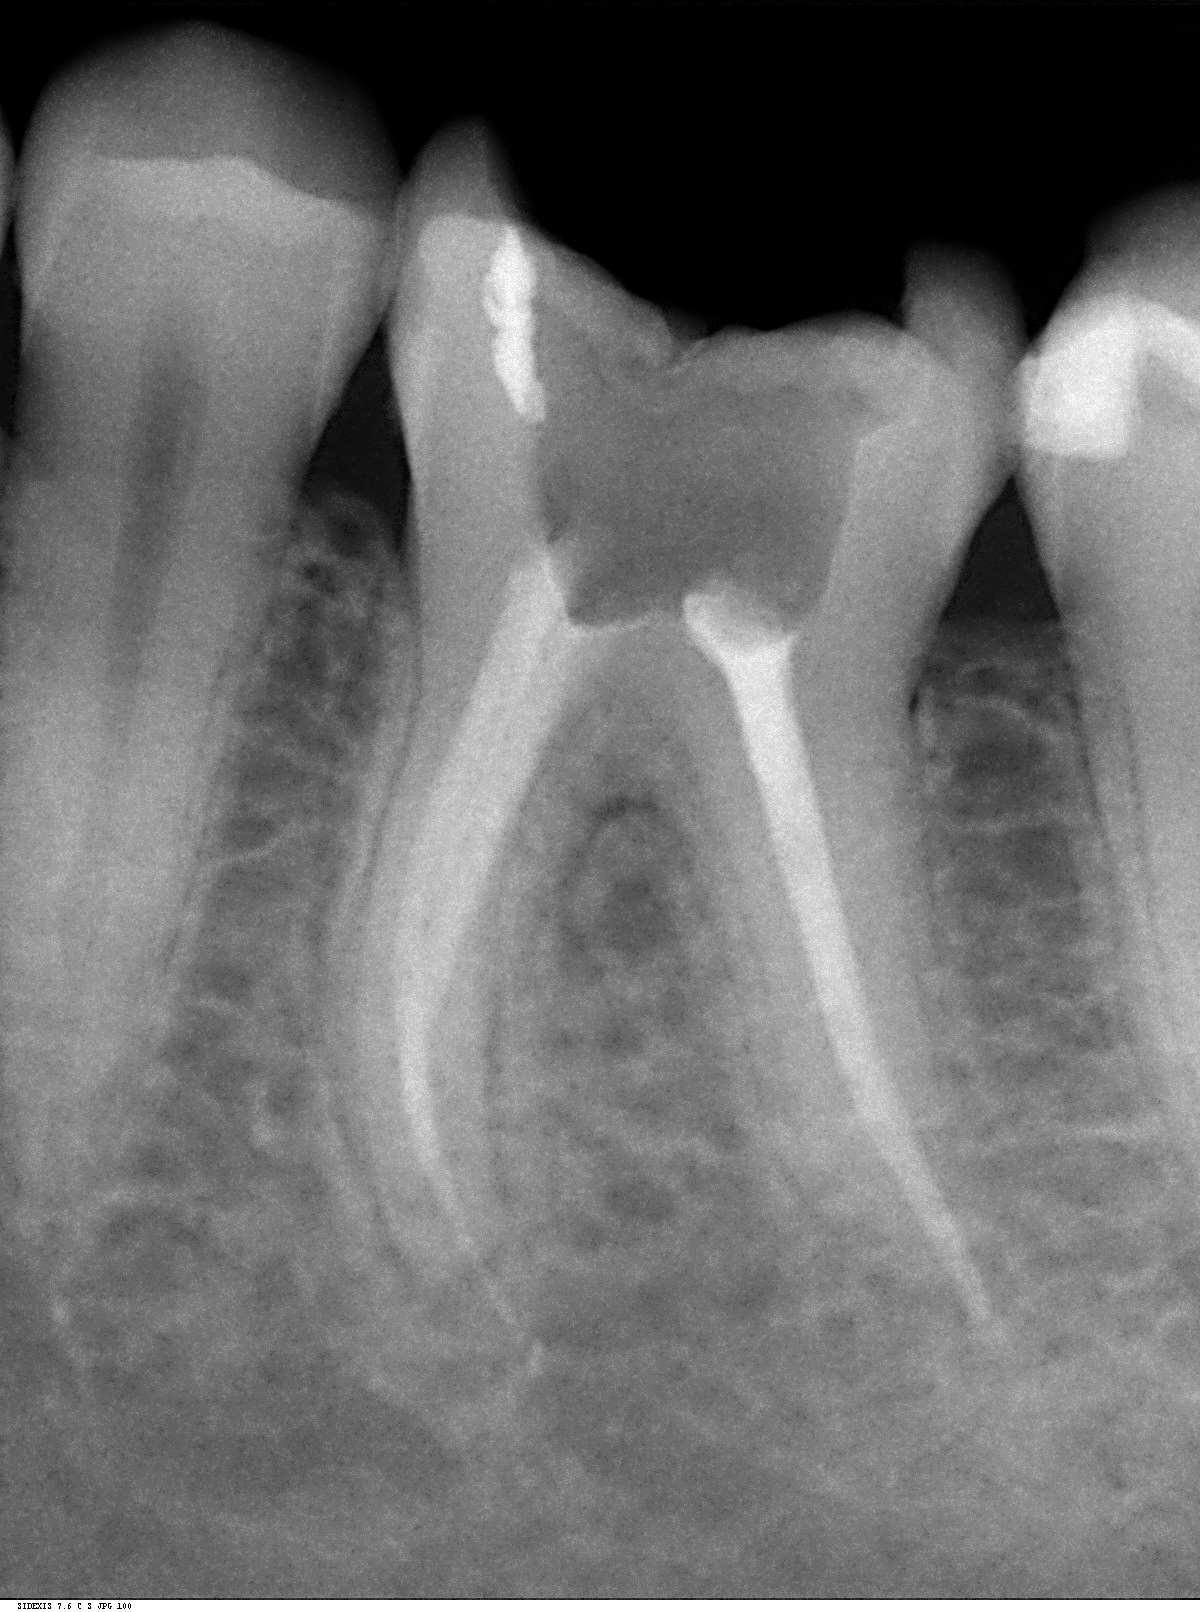

In der Behandlungsfolge wird der Wurzelkanal eröffnet, erweitert, gereinigt und abschließend mit einer Wurzelfüllpaste bakteriendicht verschlossen.

Im Rahmen der modernen Endodontie kommen in unserer Praxis besondere Maßnahmen wie die elektronische Wurzelvermessung und die maschinelle Wurzelkanalaufbereitung mit speziellen Feilen zum Einsatz.